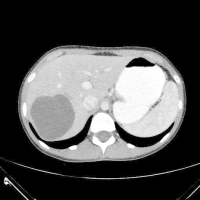

Οι ασθενείς που βρίσκονται σε υψηλό κίνδυνο απαιτούν συχνή παρακολούθηση. Αυτοί είναι οι κιρρωτικοί ασθενείς με Χρόνια Ηπατίτιδα Β, Χρόνια Ηπατίτιδα C, Χολοστατικά Σύνδρομα, NASH κα. Οι όζοι που εντοπίζωνται στο υπερηχογράφημα και είναι >1cm πρέπει να παρακολουθούνται κάθε 3-6 μήνες. Αν μεγαλώνουν τότε πρέπει να γίνεται διευρεύνηση με πολυφασική Αξονική Τομογραφία ή με Μαγνητική Τομογραφία και χρήση σκιαγραφικού.

⦁ Αξονική Τομογραφία με σκιαγραφικό (Enhanced MDCT)

⦁ Μαγνητική Τομογραφία με σκιαγραφικό (Enhanced MRI)

• Αξονική τομογραφία: μπορεί να εντοπίσει την εχινόκοκκο κύστη καθώς και τη διασπορά της σε άλλες περιοχές του σώματος. Επιπλέον, βοηθάει στο σχεδιασμό της επέμβασης αλλά και της μετέπειτα παρακολούθησης.